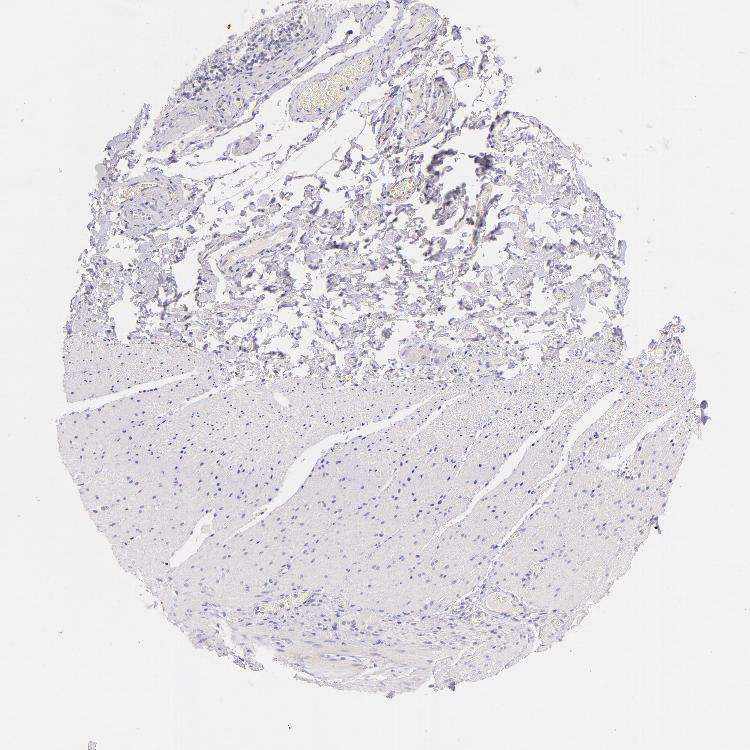

SOFT TISSUE 2 - Antibody stainingi

Antibody staining in the annotated cell types in the current human tissue is reported as not detected, low, medium, or high, based on conventional immunohistochemistry profiling in selected tissues. This score is based on the combination of the staining intensity and fraction of stained cells.

Each image is clickable and will lead to virtual microscopy that enables deeper exploration of all samples and also displays staining intensity scores, fraction scores and subcellular localization as well as patient and tissue information for each sample.

Antibody CAB000112Antibody CAB000316

Fibroblasts Not detectedMedium

Peripheral nerve Not detected-